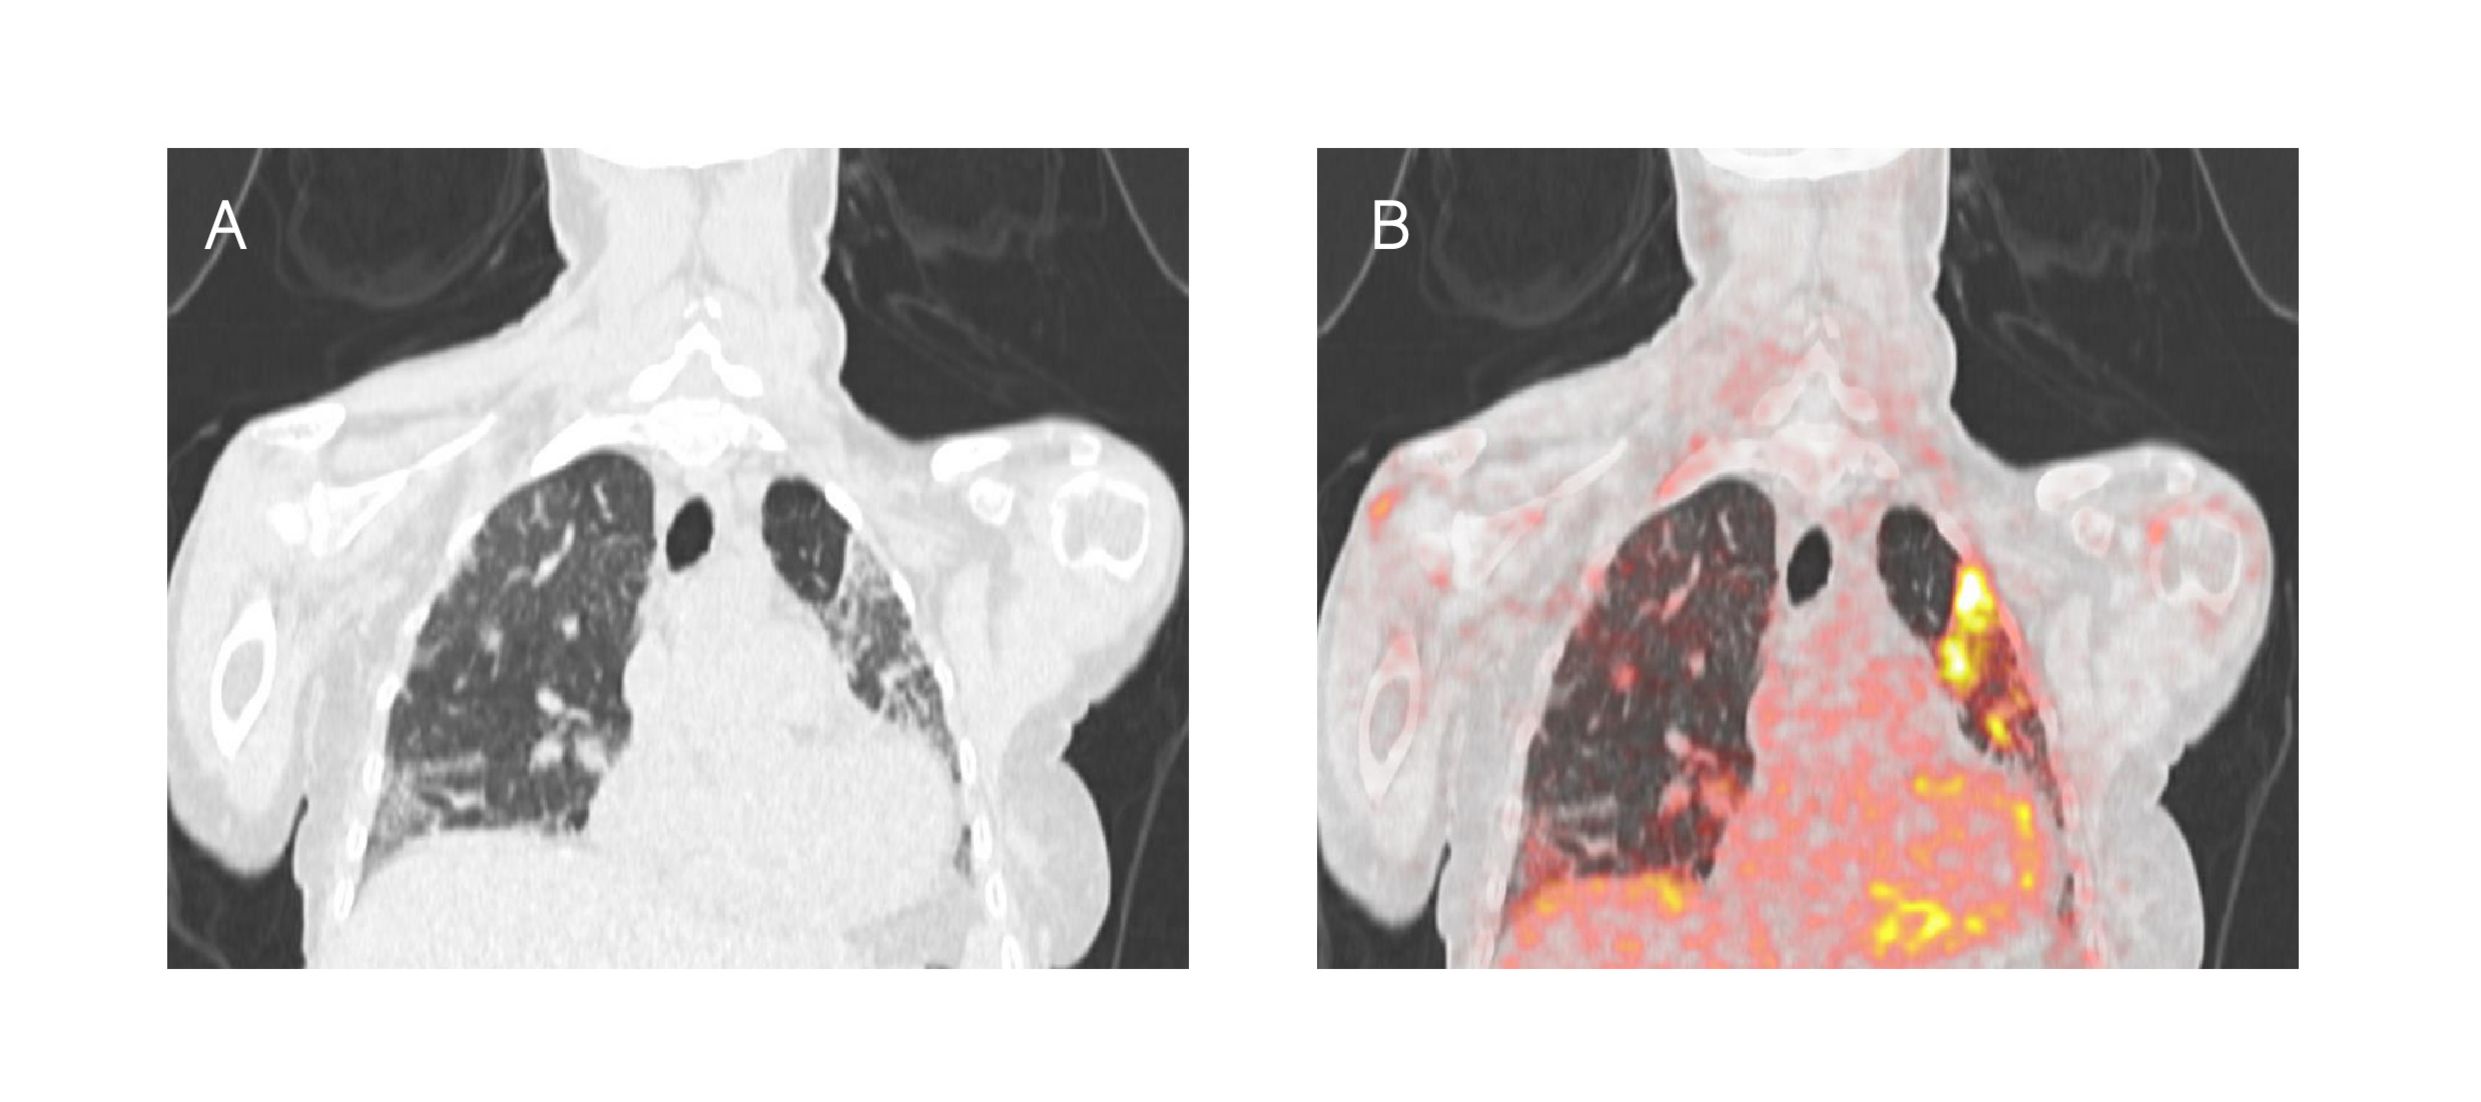

Interstitielle Lungenerkrankungen und Herzbeteiligung sind häufige Manifestationen oder Komorbiditäten rheumatischer und muskuloskelettaler Erkrankungen im Allgemeinen und von Bindegewebserkrankungen im Besonderen und tragen wesentlich zu Krankenhausaufenthalten, erhöhter Morbidität und Mortalität bei. In Zusammenarbeit mit der Abteilung für Nuklearmedizin der MUW untersuchen wir den Nutzen des ⁶⁸Ga-markierten Inhibitors des Fibroblasten-Aktivierungs-Proteins (FAPi) auf der Grundlage der Positronen-Emissions-Tomographie und der Computertomographie zur Visualisierung und Quantifizierung der Fibroblastenaktivierung in Lunge, Herz und Muskel von Patienten mit Bindegewebserkrankungen und anderen rheumatischen und muskuloskelettalen Erkrankungen.

[68Ga]68Ga-DATA5m.SA.FAPi-Aufnahme in der Lunge (Repräsentatives Bild eines Komputertomographie (A) sowie eines [68Ga]68Ga-DATA5m.SA.FAPi-PET-CT-Scans (B) von einem Patienten mit interstitieller Lungenerkrankung bei idiopathischer entzündlicher Myopathie.